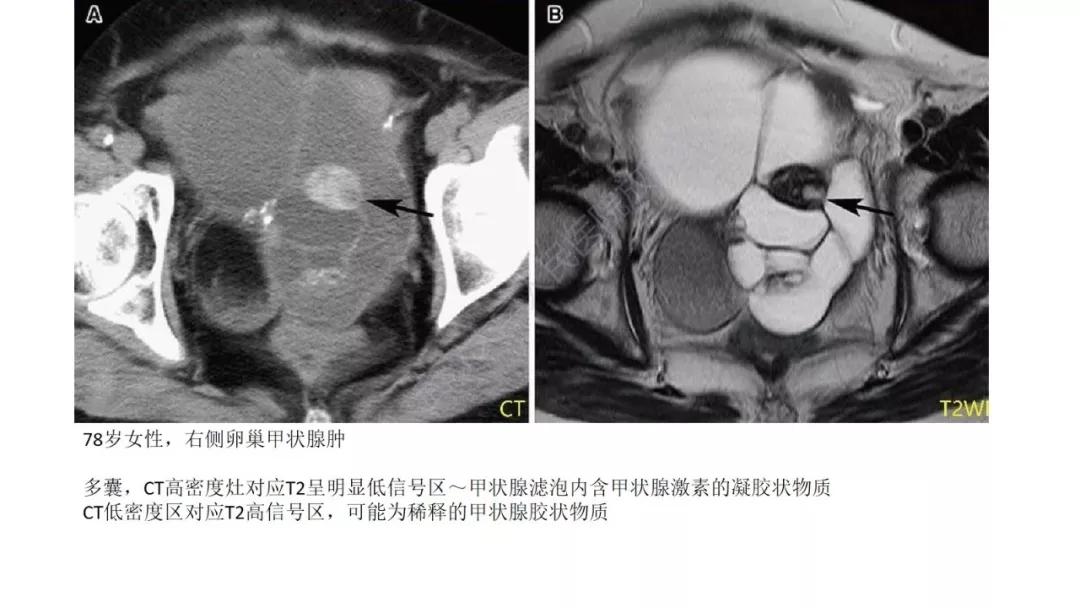

T2WI 低信号病灶:出血、平滑肌、纤维组织、卵巢甲状腺肿(凝胶)